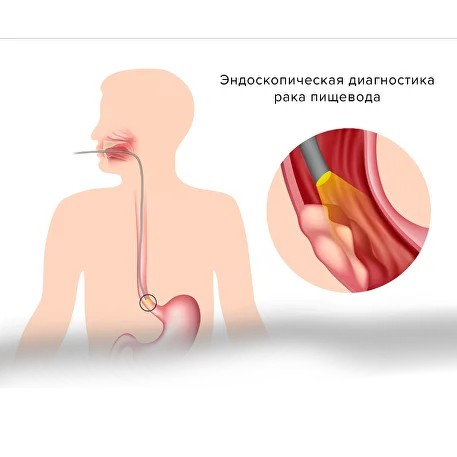

食管癌的诊断

为确诊疾病,专家会建议进行以下检查:

食管胃十二指肠镜检查(EGDS)

病变组织的组织学检查